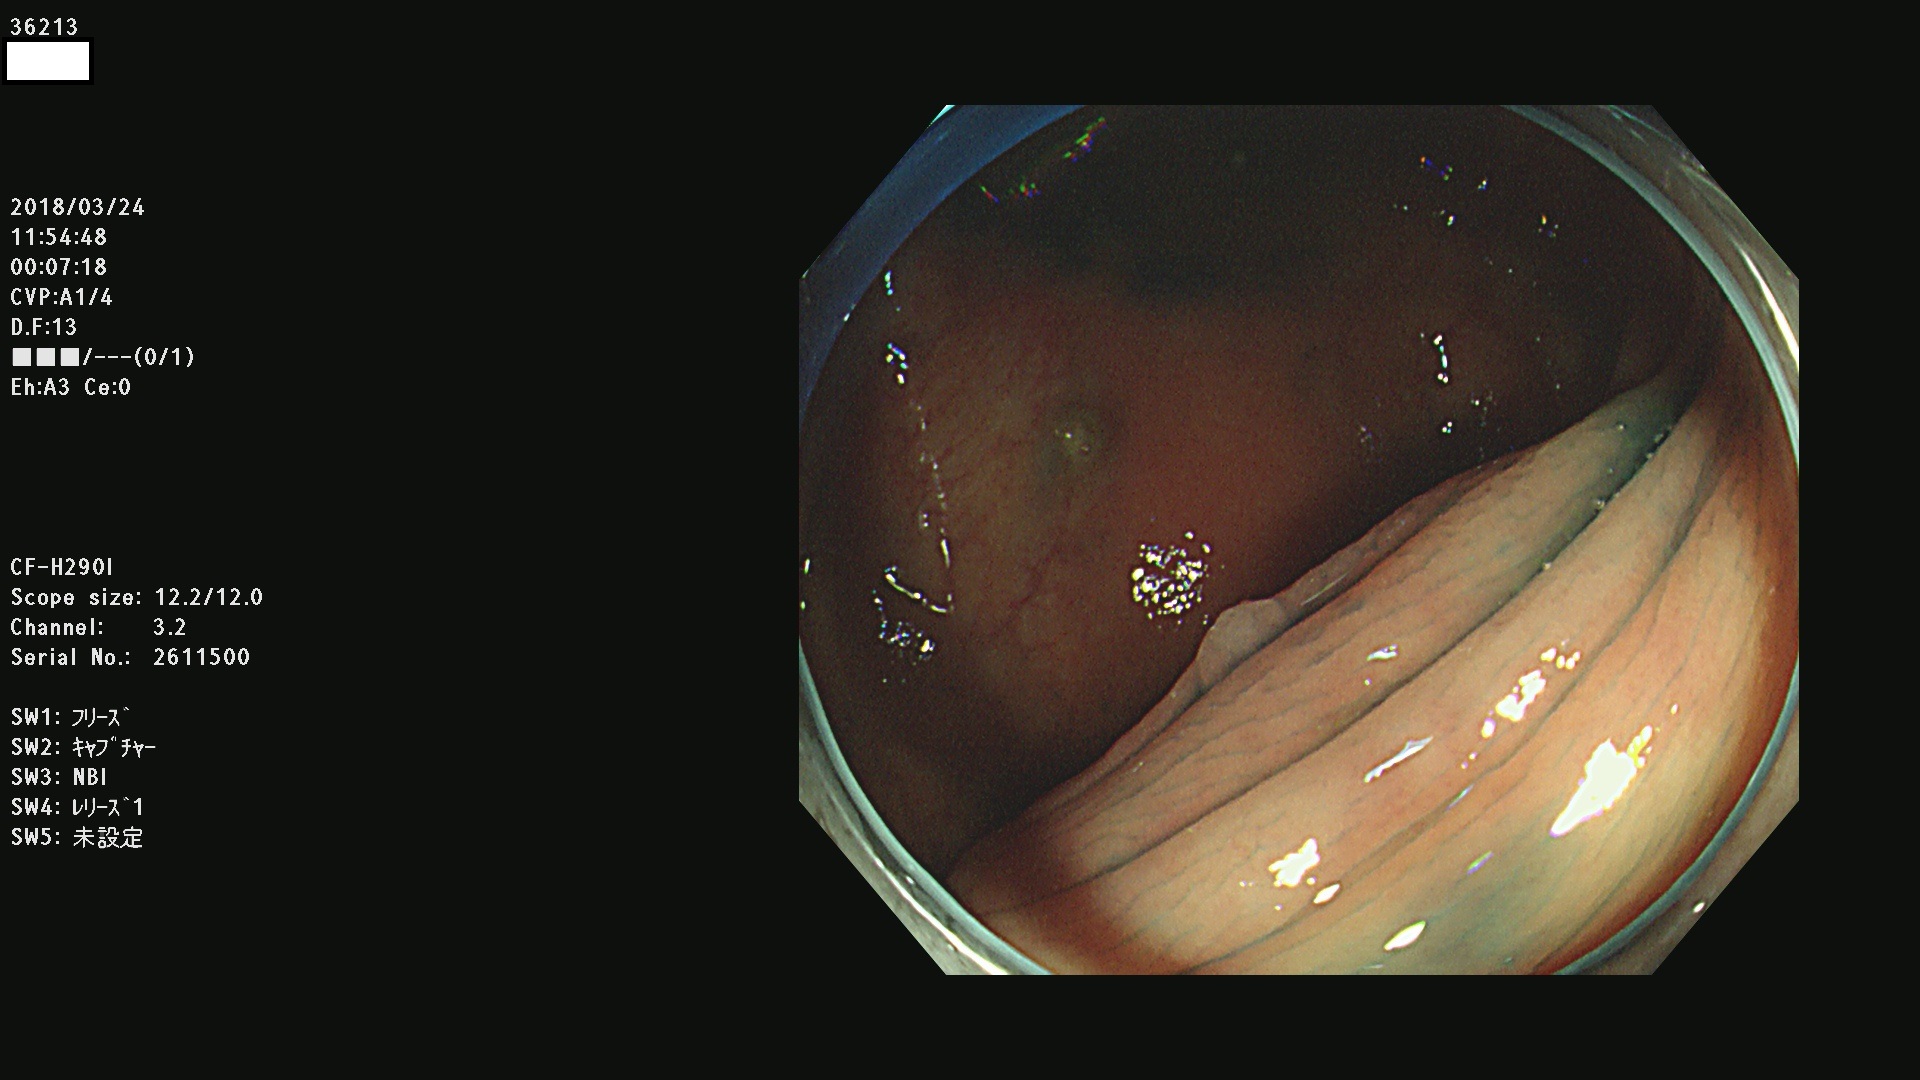

36201 36202 36203 36205 36207 36209 36210 36212 36213 36214 36215 36217 36220 36221 36222 36224 36225 36226 36227 36229 36230 36231 36232 36235 36236 36238 36240 36243 36244 36246 36247(SSAPのみ。SPS) 36248 36249 36251 36252 36253 36254 36255 36256 36257 36258 36259 36261 36262 36264 36265 36267 36269 36270 36272 36274 36275 36276 36279 36280 36281 36283 36285 36288 36289 36291 36292 36295 36296 36297 36299

発見困難で危険性の高い平坦型病変(上記100名より抽出)